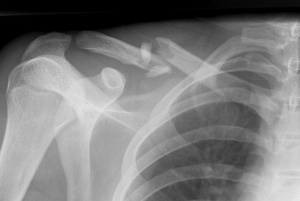

Перелом ключицы у детей диагностируется с помощью рентгенографии. Она выполняется в прямой стандартной укладке. Поставить диагноз не сложно. Если нужно отличить перелом от другой патологи, проводится МРТ или КТ.